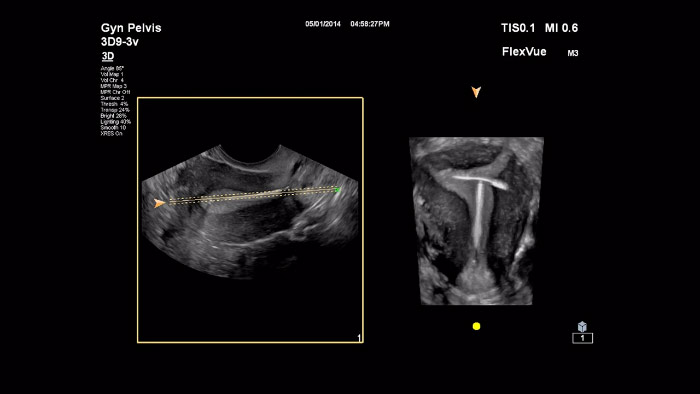

En este vídeo el Dr. Michael Ruma presenta FlexVue y RexVue Volume, herramientas avanzadas de evaluación 3D de Philips. Con FlexVue y Flexvue Volume se pueden visualizar fácilmente vistas anatómicas técnicamente difíciles a partir de volúmenes 3D, que son esenciales para el diagnóstico de patologías en obstetricia y ginecología.

En este vídeo, el Dr. Michael Ruma presenta FlexVue y la función Orthogonal View, que son las herramientas avanzadas de Philips para la evaluación 3D en casos clínicos para obstetricia y ginecología.